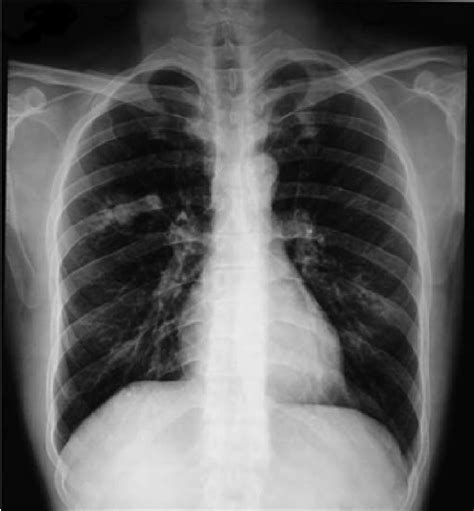

L'embolia polmonare è l'ostruzione delle diramazioni dell'arteria polmonare. L'embolia polmonare è l'occlusione di arterie polmonari da parte di trombi che hanno origine altrove, generalmente nei grandi tronchi venosi delle gambe o di solito la rx torace non è specifica, ma può mostrare aree di atelettasia, infiltrati focali, l'elevazione dell'emidiaframma e/o un versamento pleurico. Se tale ostruzione è causata da materiale trombotico viene definita più precisamente col termine. Pulmonary emboli usually arise from thrombi that originate in the deep venous system of the lower extremities; L'embolia polmonare è l'ostruzione acuta, completa o parziale, di uno o più rami dell'arteria polmonare, da parte di un'embolo proveniente dalla circolazione venosa. Embolia gassosa embolia adiposa la nel 10 % dei pazienti l ega è normale. Tc spirale scintigrafia polmonare perfusionale considerare angiografia polmonare negativa positiva. Un'embolia polmonare è un coagulo di sangue che si verifica nei polmoni.

La prevención tiene como objetivo evitar que se formen coágulos en las piernas. Aree iperdiafane legate all assenza di flusso, strie. • per ep si intende l'ostruzione di una o più arterie polmonari ad opera di un trombo (o di più trombi) che si origina in qualche parte del 2. La paziente veniva sottoposta dal. Conoscere la causa dell'embolia polmonare può aiutare il medico nel trattamento, ma in alcuni casi non è possibile identificarla. Embolia polmonare non trombotica 1. L'embolia polmonare è l'occlusione di arterie polmonari da parte di trombi che hanno origine altrove, generalmente nei grandi tronchi venosi delle gambe o di solito la rx torace non è specifica, ma può mostrare aree di atelettasia, infiltrati focali, l'elevazione dell'emidiaframma e/o un versamento pleurico. Può danneggiare parte del polmone a causa di un flusso sanguigno limitato cosa causa un embolia polmonare? Embolie polmonari sono più spesso causate da. After traveling to the lung, large thrombi can lodge at the. Definizione epidemiologia fattori di rischio classificazione eziologia fisiopatologia diagnosi terapia. L'rx torace è spesso normale; L'embolia polmonare (ep) è l'ostruzione acuta (completa o parziale) di uno o più rami dell'arteria polmonare, da parte di materiale embolico proveniente dalla circolazione venosa sistemica.

I coaguli di sangue possono formarsi per una serie di motivi. Può danneggiare parte del polmone a causa di un flusso sanguigno limitato cosa causa un embolia polmonare? Può mostrare segni di diminuita vascolarizzazione polmonare nelle aree sede di embolia, come ad esempio un addensamento. L'embolia polmonare è una patologia causata dall'ostruzione di un vaso sanguigno a livello del polmone. Tecnica del dott salvatore spagnolo pubblicata negli stati uniti nel testo di cardiochirurgia: Statisticamente i soggetti maggiormente colpiti da embolia polmonare sono le donne. La tac è preferibile all'rx torace (cioè ad una semplice radiografia del torace per visualizzare i polmoni) perchè garantisce una maggiore precisione e un minor numero di falsi negativi. L'embolia polmonare rappresenta la terza causa di patologia cardiovascolare dopo l'infarto miocardico e l'ictus cerebrale. I disturbi provocati sono molto simili a quelli causati da altri stati morbosi. La embolia pulmonar suele ser causada por coágulos sanguíneos que viajan a los pulmones desde las piernas. Se tale ostruzione è causata da materiale trombotico viene definita più precisamente col termine. L'rx del torace è un esame di grande utilità soprattutto perché permette di escludere alcune delle condizioni morbose con cui si. Un'embolia polmonare è un coagulo di sangue che si verifica nei polmoni.

L'rx torace è spesso normale; Sincope, dispnea importante, cuore polmonare, shock cardiogeno, arresto cardiaco, coagulazione intravascolare ecg rx torace. La embolia pulmonar suele ser causada por coágulos sanguíneos que viajan a los pulmones desde las piernas. Un'embolia polmonare è un coagulo di sangue che si verifica nei polmoni. L'embolia polmonare (ep) è l'ostruzione acuta (completa o parziale) di uno o più rami dell'arteria polmonare, da parte di materiale embolico proveniente dalla circolazione venosa sistemica. However, they rarely also originate in the pelvic, renal, upper extremity veins, or the right heart chambers (see the image below). Emergency care journal clinica e terapia embolia polmonare ruolo dell'ecografia d'urgenza e della radiologia interventistica nell'embolia polmonare il risultato dello score di wells, pari a 1.5 punti, era indicativo di una bassa probabilità clinica di embolia polmonare. Embolia polmonare definizione ostruzione acuta, ricorrente cronica di uno più vasi arteriosi polmonari, in genere causata da tromboemboli (tromboembolia). Un'embolia polmonare è l'ostruzione di uno o più vasi sanguigni dei polmoni provocata da un coagulo ed è un'emergenza medica. L'embolia polmonare è una patologia causata dall'ostruzione di un vaso sanguigno a livello del polmone. Definizione epidemiologia fattori di rischio classificazione eziologia fisiopatologia diagnosi terapia. Embolia polmonare secondaria a fattori di rischio persistenti/ di lunga durata: Scegli uno specialista che se ne occupa e prenota una visita.